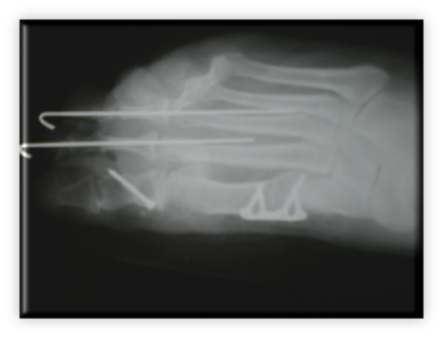

ΚΑΤΑΓΜΑ ΕΞΩ ΣΦΥΡΟΥ ΑΝΤΙΜΕΤΩΠΙΣΘΕΝ ΣΕ ΧΕΙΡΟΥΡΓΕΙΟ ΜΑΧΗΣ ΣΤΟ ΑΦΓΑΝΙΣΤΑΝ ΑΠΟ ΤΗΝ ΕΛΛΗΝΙΚΗ ΑΠΟΣΤΟΛΗ 10. Ποδοκνημική - Άκρος πόδας Αρχική σελίδα 10. Ποδοκνημική - Άκρος πόδας Ορθοπαιδικές Παθήσεις 2. Ώμος 1. Αυχένας 3. Αγκώνας 5. Σπονδυλική στήλη 6. Ισχίο 7. Μηρός 8. Γόνατο 9. Κνήμη 10. Ποδοκνημική - Άκρος πόδας 4. Άκρα χείρα - Πηχεοκαρπική